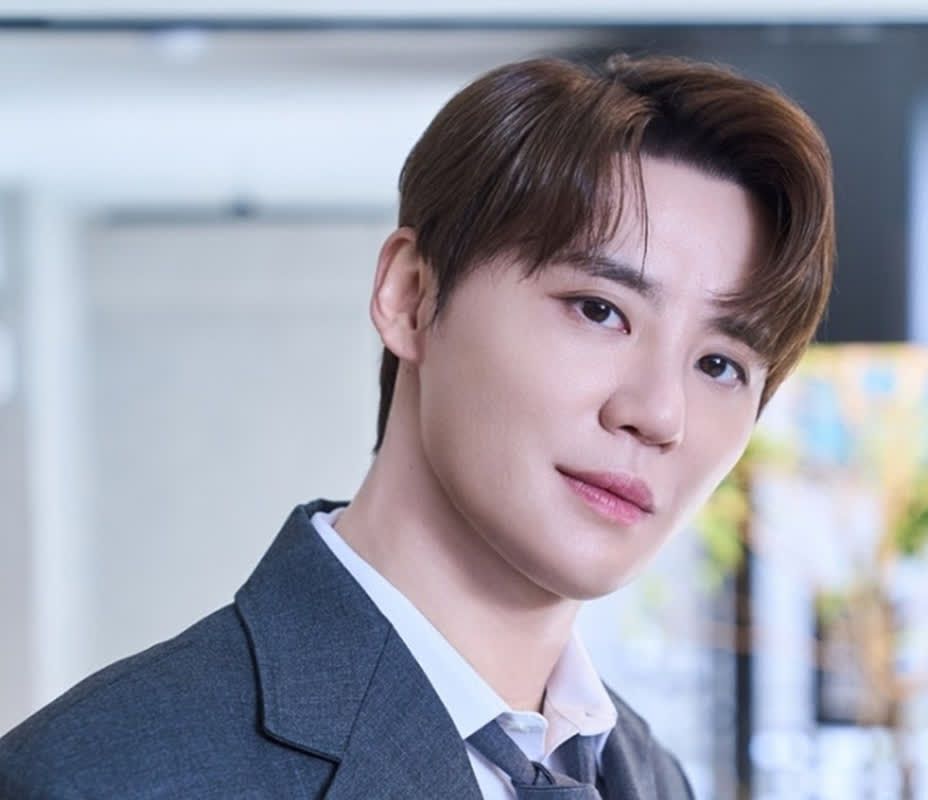

ソウル大学小児病院の小児精神科で働くキム・ジェウォン教授は、小児うつ病を予防するために最も重要なのは、心身ともに健康な環境を整えることだと強調している。ゲームやスマートフォンの代わりに、体を動かしてリラックスできる時間と空間を確保すべきだ。忙しい教育環境の中で、親が子どもにとっての息抜きの機会を積極的に作る必要があると説明している。また、家庭でも実施可能なうつ病スクリーニングテスト(PHQ-9など)を年1回定期的に行うことも、早期発見や予防につながる。